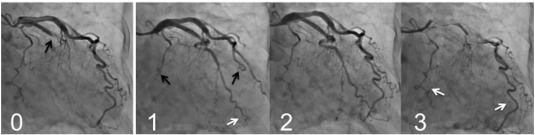

Mechanical restoration of coronary blood flow by percutaneous coronary intervention (PCI) often results in tissue hypoperfusion in patients with STEMI; this is reperfusion injury in the microvasculature, known as the no-reflow phenomenon [25] ;  [26], or more recently as microvascular obstruction [27] ;  [28]. My colleagues and I reported that PCLeB was consistently followed by angiographically excellent microcirculation recovery [2]; [3]; [4]; [5] ;  [6]. The coronary angiography findings of a representative patient are presented in Fig. 2. This patient had a totally occluded obtuse marginal artery. After completion of PCI using PCLeB, coronary blood flow in the obtuse marginal artery appeared to be faster than that in the other coronary arteries. Furthermore, the washout of the contrast medium from the obtuse marginal artery appeared to be faster still, indicating that microcirculation recovery was apparently augmented. These angiographic observations have been confirmed by a more quantitative approach. We reported that the mean corrected Thrombolysis in Myocardial Infarction (TIMI) frame count of 55 consecutive STEMI patients treated using PCLeB was 20.1 ± 10.1 frames (normal value 21 frames) [5]. Among these patients, 30 so far have returned for follow-up coronary angiography and have shown no angiographic restenosis. In these 30 patients, the corrected TIMI frame counts immediately after PCI completion (19.1 ± 9.3 frames) were significantly smaller than those in the chronic phase (27.4 ± 12.2 frames, p < 0.0001). These results were in stark contrast to the no-reflow phenomenon, and the results obtained indicated more than its prevention. Because our approach did not include any pharmacological intervention, the consistently observed excellent recovery of microcirculation can be viewed as an emergence of what it truly is, unveiled by our approach. Reactive hyperemia caused by endogenous vasodilators, such as adenosine or nitric oxide, is known to be transiently observed during the early reperfusion period following ischemia. The reason for the transient nature of reactive hyperemia is unknown. However, the consistently observed excellent microcirculation recovery in our studies suggests that reactive hyperemia had been prematurely abolished by microvascular reperfusion injury that developed immediately after reperfusion. Successful attenuation of microvascular reperfusion injury by our approach might possibly unveil the true nature of reactive hyperemia, i.e., long-lasting reactive hyperemia, for the first time ever. Hypercontracture obliterates microcirculatory coronary flow by compressing the vessel walls from outside; this action has been incorporated into the mechanisms of the no-reflow phenomenon [29] ;  [30]. The consistently observed excellent microcirculation recovery may indicate that our approach, targeting hypercontracture, has been successful.

Fig. 2.

Coronary angiography (CAG) findings of a representative patient (an 81-year-old woman), before and after percutaneous coronary intervention (PCI).

Panel 0: CAG before PCI. The obtuse marginal artery was totally occluded (black arrow). Panel 1: The early phase of the final CAG view after PCI completion. The contrast medium reached the far end of the obtuse marginal artery (white arrow) while still only extending halfway through the left anterior descending artery and the main trunk of the left circumflex artery (black arrows). Panel 2: The mid phase of the final CAG view. Panel 3: The late phase of the final CAG view. The contrast medium still remained in both the left anterior descending and the main trunk of the left circumflex arteries (white arrows), while it had already washed out from the obtuse marginal artery.